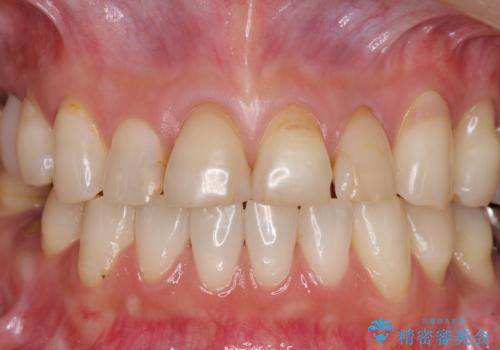

口元の印象が明るくなり、人前で気にせずに笑えるようになりました。

以前矯正治療をされ、その時には歯列が整ったので満足されたそうですが、若干の後戻りにより隙間ができ、矯正治療前に治療していた虫歯の跡が気になったため、オールセラミックによる審美治療を希望されました。

目立つ範囲である前歯4歯をオールセラミッククラウンにて補綴することとしました。